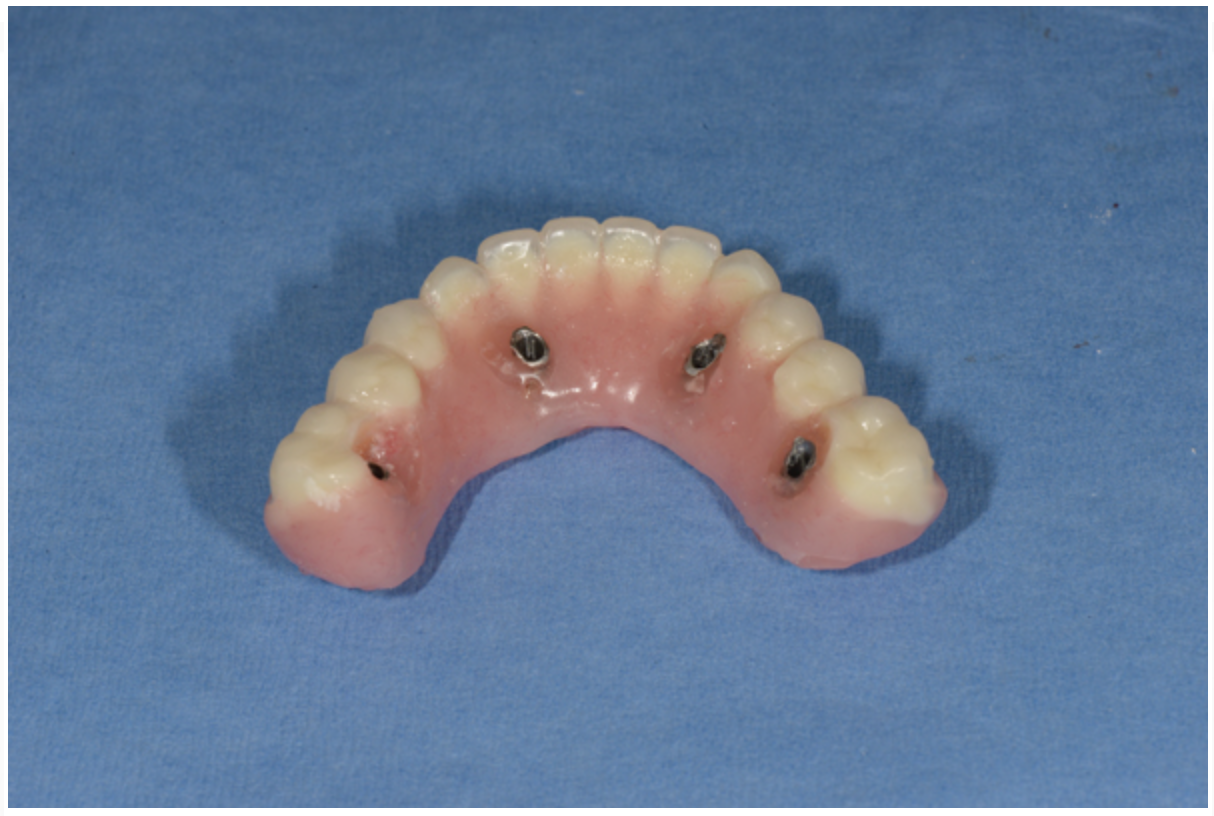

Fig 16. Indirect denture conversion—The indexed provisional prosthesis is modified for passive attachment of the posterior titanium cylinders to the prosthesis using heat-cured acrylic under pressure. This process is repeated for the anterior indexed implants, leading to a higher quality provisional with increased strength.

Figure 16